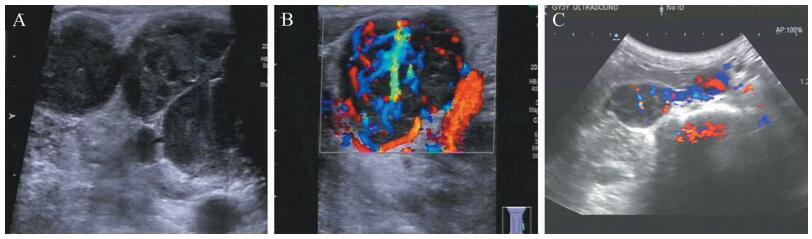

二、实验室及辅助检查血常规:血红蛋白75 g/L,其余项目无明显异常。结核杆菌抗体TB-IgG阴性。肿瘤抗体无异常。微小病毒B19 IgG抗体阳性,EB病毒抗体无异常。超声检查提示左侧颈侧区见多个类圆形肿大淋巴结,最大约3.5 cm×3.0 cm,纵横比<2,内部回声低、不均匀,皮髓质分界不清,边界清晰,部分融合(图 1A)。彩色多普勒超声检查(彩超)示上述肿大淋巴结内部血流信号丰富,呈“树枝状”分布(图 1B)。腹膜后区腹主动脉中段旁见一类圆形低回声团,大小约37 mm×25 mm,边界清晰,内部回声欠均匀;彩超示上述低回声团内部可见较丰富条状彩色血流信号(图 1C)。胸部、全腹部CT平扫+增强示双侧颈部占位病变(以左侧明显),考虑为恶性病变、转移瘤。双肺散在结节,性质待定,不排除转移瘤、增殖灶。纵隔内数个稍微增大淋巴结。右侧腹膜后下腔静脉旁肿块,不排除转移瘤、增大淋巴结。肿瘤氟代脱氧葡萄糖(18F-FDG)代谢显像:全身多区域淋巴结肿大并18F-FDG代谢增高。头颅MRI未见明显异常。

图 1 一例CD20阴性DLBCL患者的超声检查图 A:二维超声示淋巴结肿大,呈类圆形,内部回声低、不均匀,皮髓质分界不清,边界清晰,部分淋巴结融合;B:彩超示淋巴结内部血流信号丰富,呈“树枝状”分布;C:彩超示低回声团内部丰富条状彩色血流信号 |